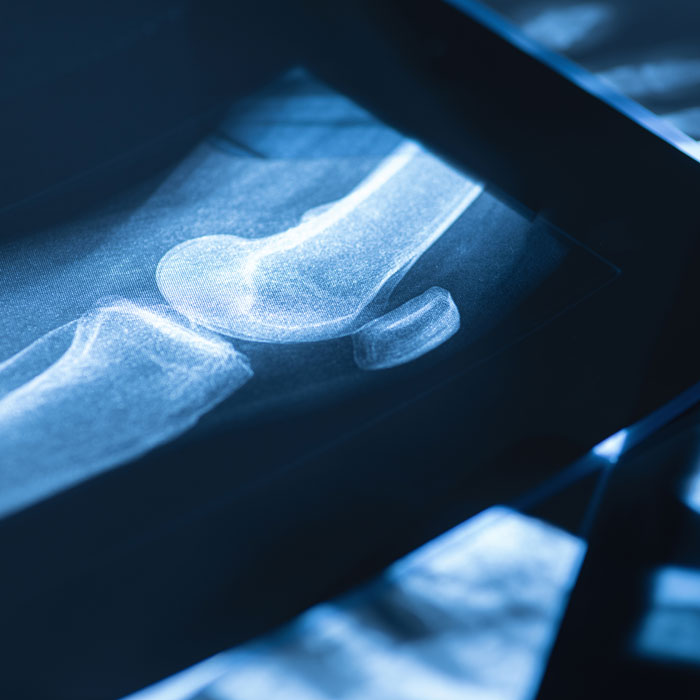

Imaging:

X-rays, MRI, CT, or PET scans to check for bone damage or tumors